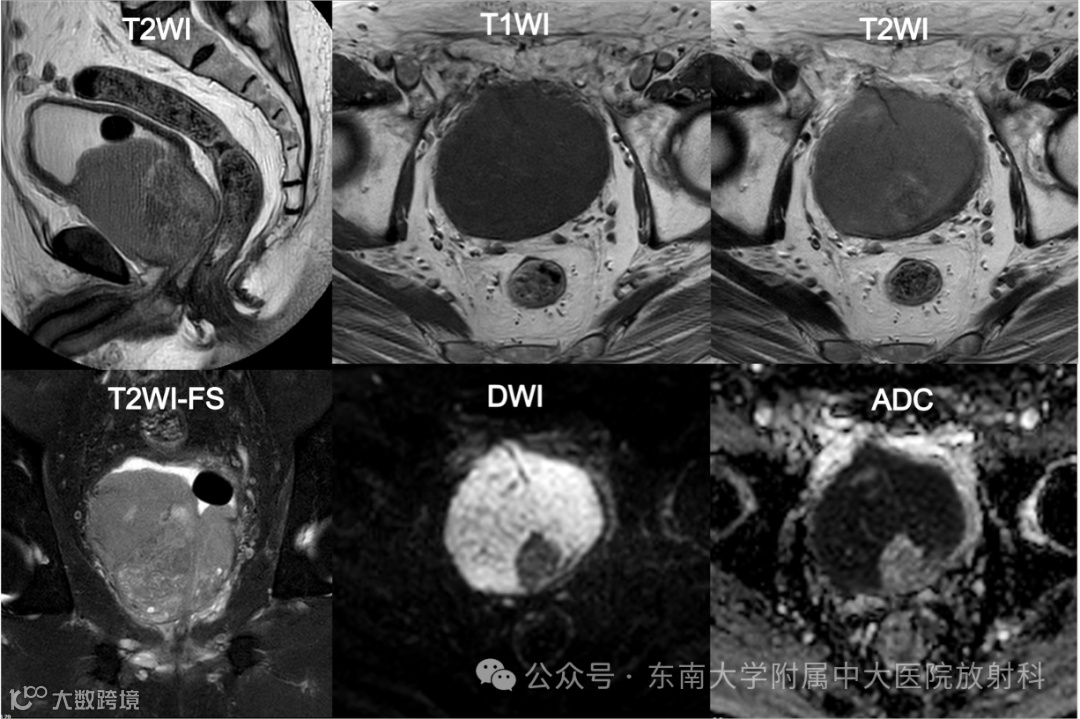

主诉:发现肉眼血尿3年余,加重1周

现病史:患者3年前无明显诱因下出现无痛性肉眼血尿,无血块,自然缓解,未予重视;1 周前加重,全程肉眼血尿;夜间小便 6-8 次,有尿频尿急,无尿痛,无排尿困难,无畏寒发热,无腰痛腹痛等;门诊拟以“前列腺增生”收住入院

实验室检查: LDH:432U/L ↑ (参考值100-240U/L)

fPSA:1.48ng/mL ↑ (参考值0-1ng/mL)

tPSA: 8.32ng/mL ↑ (参考值0-4ng/mL)

影像号:1217119452 2025-09-08 盆腔MR平扫

影像学表现